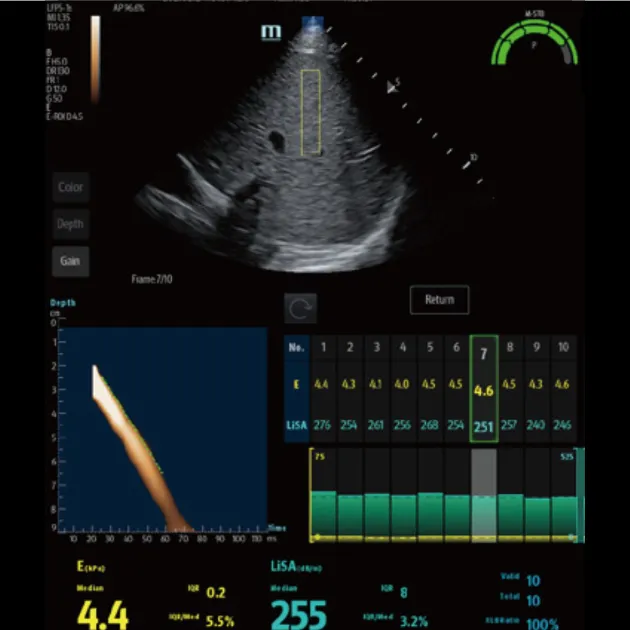

Количественный анализ ригидности печени Обеспечивает количественное определение жесткости печени и стадии фиброза печени с помощью технологии переходной эластографии

Количественный анализ стеатоза печени Количественная оцененка тяжести стеатоза печени с помощью технологии LiSA (поглощения ультразвука в печени).

Advanced ViTE (визуализированная транзиторная эластография)

- Проводить количественное выявление и оценку фиброза и стеатоза печени под визуальным контролем 2D-ультразвука в режиме реального времени

- Позволяет избежать образования кровеносных сосудов и повреждений, повысить точность и достоверность измерения

- Значительно снижает сложность операции, повышает точность и повторяемость количественных измерений

Быстрое интеллектуальное получение данных Q-сканирования

- Нажатием одной кнопки можно автоматически и непрерывно получать 10 групп эффективных данных и проводить интеллектуальный анализ

- Точные и достоверные результаты обнаружения могут быть получены немедленно, всего через 7 секунд после позиционирования

Надежный показатель контроля качества

- Индекс давления (P): качественный контроль давления зонда

- Индекс стабильности движения (m-STB): обеспечивает стабильность дыхания

- Четкая индикация с другим цветом для улучшения контроля качества во время обследования